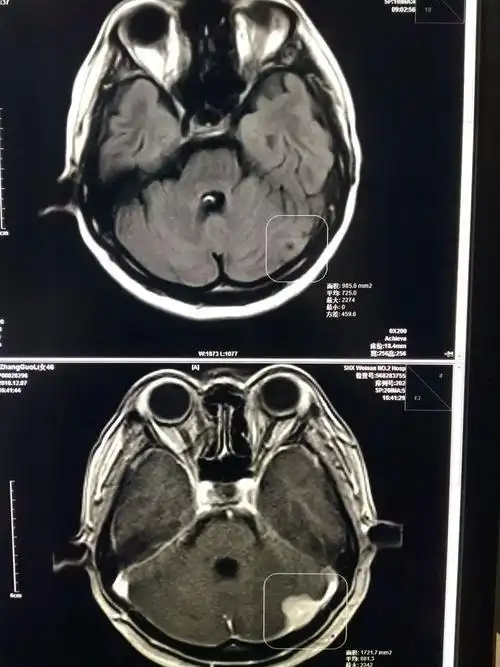

67超急性期大面积脑梗死ct平扫表现

手把手教你基础颅脑mr平扫及后处理